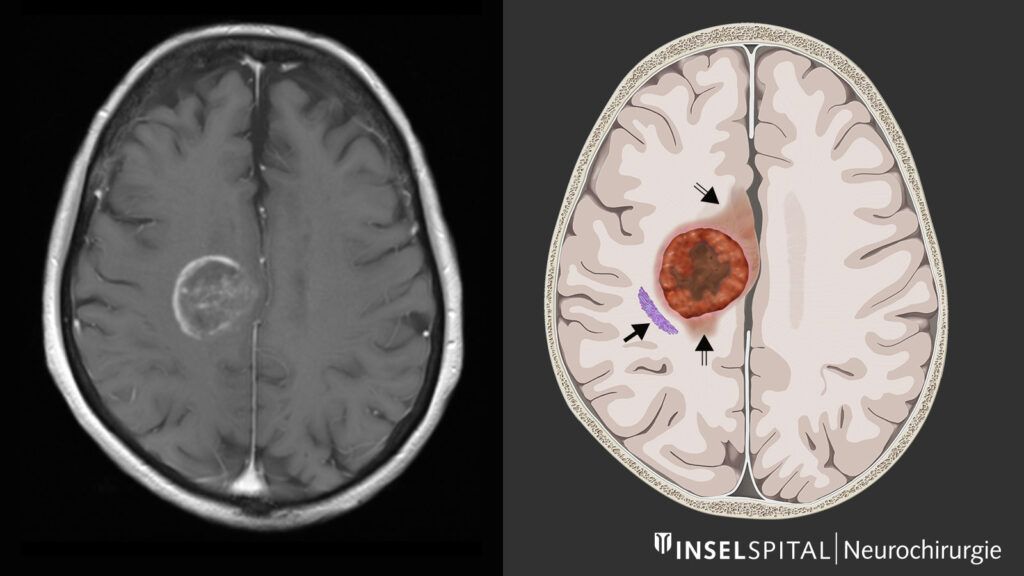

Glioblastomul este cea mai frecventă formă de cancer primar al creierului, având o evoluţie rapidă şi un prognostic rezervat. Una dintre dificultăţile terapeutice majore pentru tratament este faptul că aceste tumori sunt considerate „reci”, pentru că nu declanşează spontan o reacţie imună suficientă, spre deosebire de tumorile „calde”, mai sensibile la imunoterapii.

Inovaţia majoră constă în modul de livrare: în loc de injectare intracerebrală, nanomedicamentul este administrat ca picături nazale. Traseul urmat de particule a fost urmărit în timp real şi a arătat că acestea se deplasează de-a lungul nervului trigemen, principala cale nervoasă care conectează structurile feţei cu creierul, ajungând în zona tumorală.